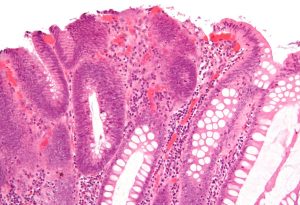

Rákvakcina és immunterápia együttes erejével semlegesíthetőek a rosszindulatú daganatok

A rák elleni gyógymódok már hosszú ideje a kemoterápiára és a sugárkezelésre vannak szűkítve, az elmúlt években azonban egyre több új eljárást dolgoztak ki, melyekkel kiváló eredményeket értek el a daganatos megbetegedések kezelése terén.